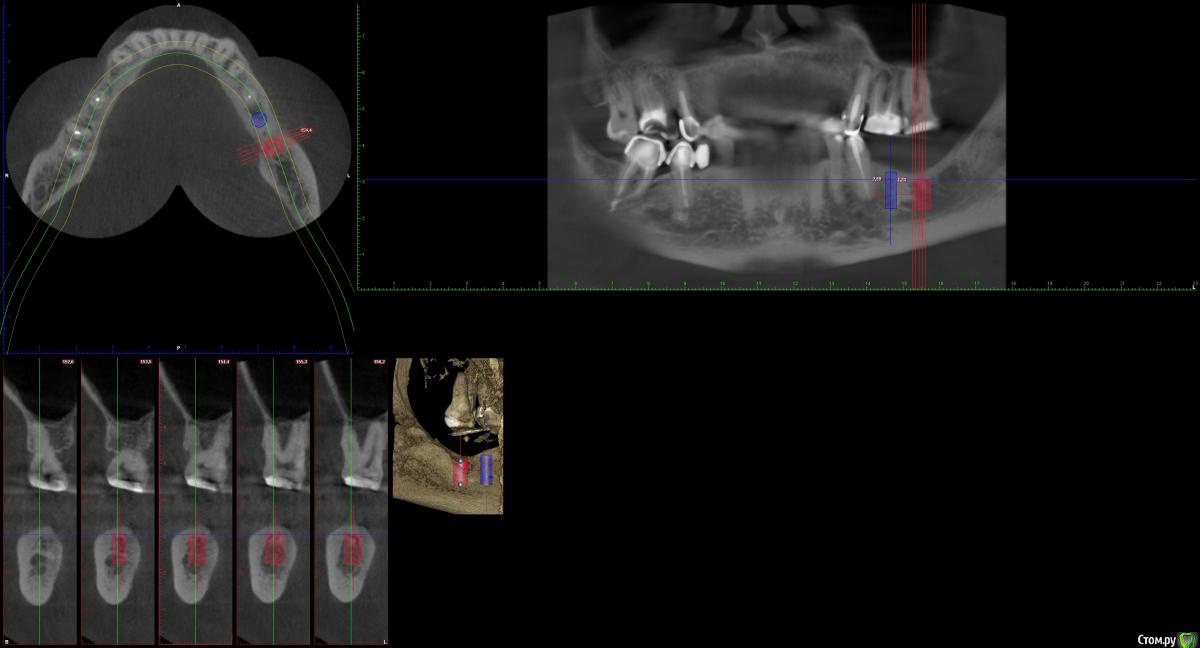

indie Опубликовано 4 октября, 2018 Поделиться Опубликовано 4 октября, 2018 Здравствуйте, колеги. Решил заняться имплантацией, думал выбирать только идеальные случаи, по Гудману так сказать. Но таких оказалось не больше 1-2 месяц, потому взялся за не совсем идеальные. По этой причине нужна помощь опытных врачей в планировании и прогнозировании возможных осложнений. Пац. 52 года. КТ прилагаю . Планируются имплантанты в позицию 36 37 MIS C1. 36 - 4.2x10mm, 37-5x8mm. Что смущает, во первых вертикальный дефицит твердых и мягких тканей, особенно в зоне 37, во вторых стоит ли вообще ставить имплантат в позицию 37. Если ставить, то можно ли обойтись без аугментаций? Ну и вообщем интересно, какой стратегии держатся в подобных не идеальных ситуациях? Спасибо. Ссылка на комментарий

indie Опубликовано 4 октября, 2018 Автор Поделиться Опубликовано 4 октября, 2018 Десневыми трансплантатами пока не владею, ну не пробовал, хотя читаю много. Ну разве что при открытии имплантата смещал лоскут букально и ушивался кругом формика, но это когда есть что смещать. У даного пац. зона кератинизированой десны норм., ширину измеряю при дальнейшем планировании, пока только кт смотрел,но меня смущает больше толщина. В таких случаях я пробую имплант углублять на 2-3мм, но тут в 37 некуда, а короче 8мм у МИСа нет. Просто был случай когда в подобной ситуации дефицита кости и десны оголилась заглушка резорбция на 2 ветка лазер лока, так званого, при длине 8мм. Поэтому и стал вопрос можно делать ли такие случаи без ССТ и как, или без аугментации десны не стоит. Спасибо за ответ за срез извините, не досмотрел. Ссылка на комментарий

indie Опубликовано 4 октября, 2018 Автор Поделиться Опубликовано 4 октября, 2018 (изменено) 36 берите 8мм,это конус,нужно будет заглублятьДа, стараюсь на 2-3мм субкрестально. А стоит ли вообще в 37 ставить тогда? И вопрос по субкрестальной позиции в Д3 нет проблем, а вот Д1-Д2 иногда не стает, торк растет и имплант прокручиваться начинает. Фрезу нужно брать на 3мм длинее и протокол весь до того же диаметра что имплант, плюс контрасилки? Просто хочется не сильно розвалить ложе, а оно потом не стает как планировал. Изменено 4 октября, 2018 пользователем indie Ссылка на комментарий

TIGER Опубликовано 8 октября, 2018 Поделиться Опубликовано 8 октября, 2018 Да, стараюсь на 2-3мм субкрестально. А стоит ли вообще в 37 ставить тогда? И вопрос по субкрестальной позиции в Д3 нет проблем, а вот Д1-Д2 иногда не стает, торк растет и имплант прокручиваться начинает. Фрезу нужно брать на 3мм длинее и протокол весь до того же диаметра что имплант, плюс контрасилки? Просто хочется не сильно розвалить ложе, а оно потом не стает как планировал. антагонист же есть,надо и 37 ставить Ссылка на комментарий